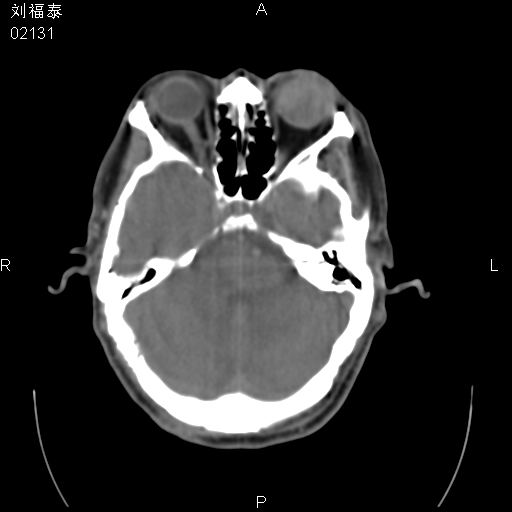

以下是引用余辉在2008-3-4 14:00:00的发言:[br]考虑左眼球黑色素瘤或血管源性肿瘤可能性大,建议增强检查

以下是引用余辉在2008-3-4 14:00:00的发言:[br]考虑眼球黑色素瘤或血管源性肿瘤可能性大,建议增强检查

以下是引用zsl6918在2008-3-4 15:08:00的发言:[br]现有征象只能提示球内出血,视网膜脱落,至于是否为肿瘤性病变需mri检查。